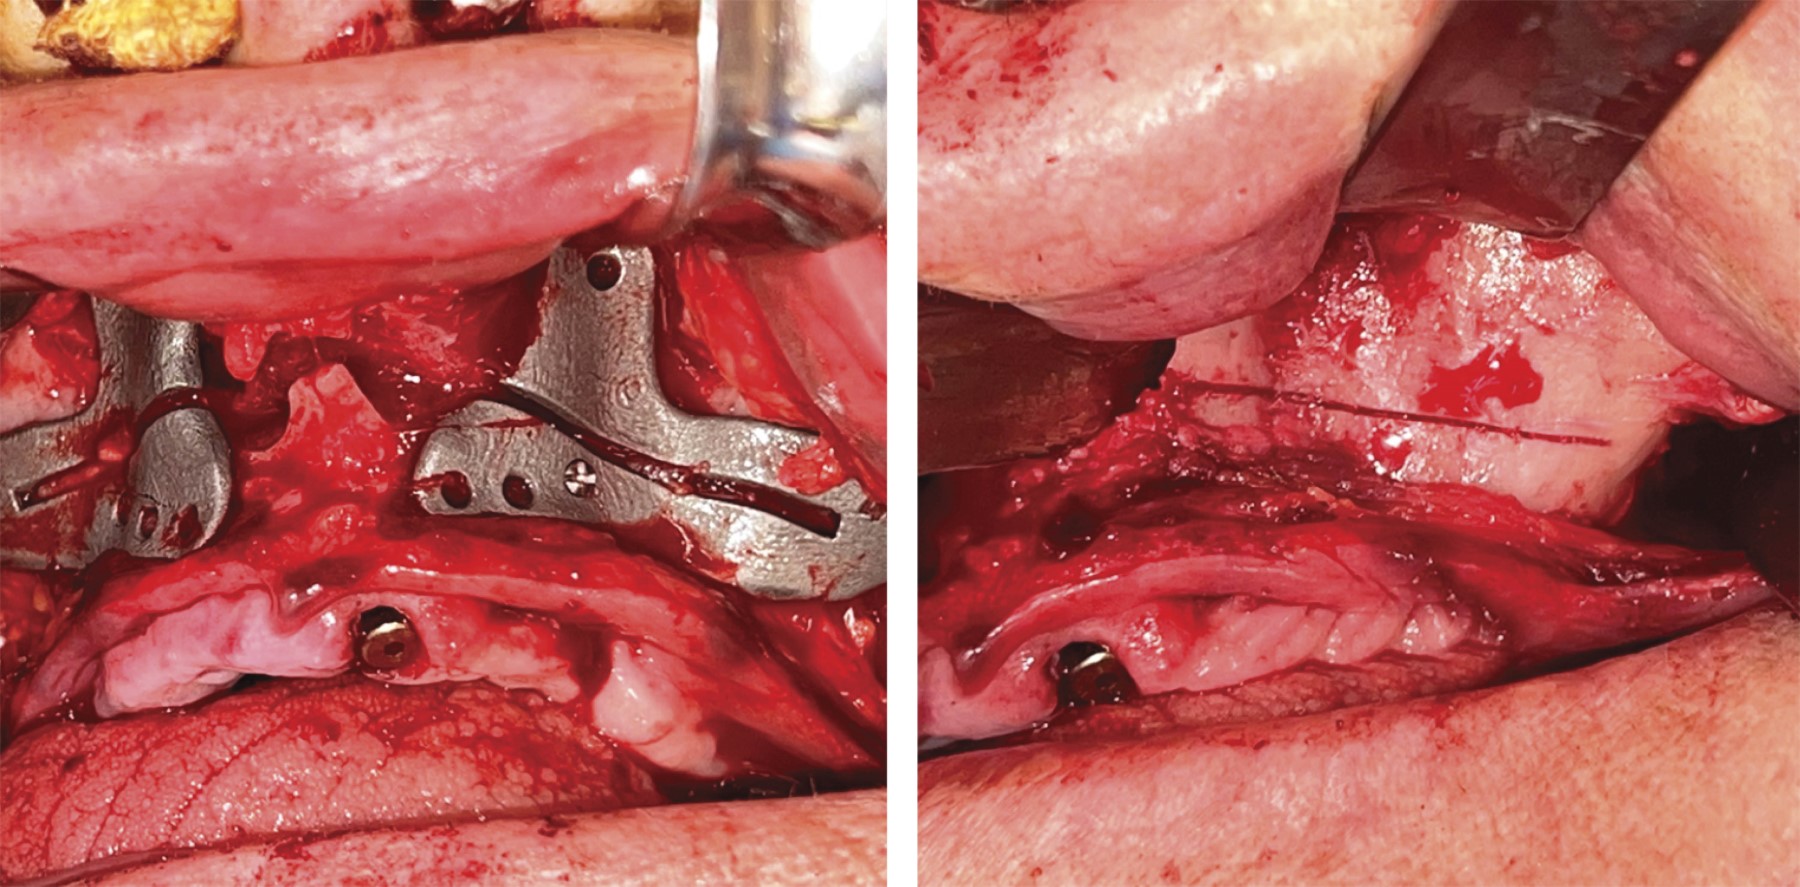

• 3. Fractura Le Fort I controlada del maxilar y su reubicación con avance programado, fijado con placas y tornillos de osteosíntesis según el protocolo dual utilizado por el autor. Se prestó atención a la integridad de la mucosa nasal y la membrana de Schneider, así como a la optimización de la proyección de la punta de la nariz mediante el soporte de la región nasolabial para lograr un buen resultado estético y funcional.

• 4. Colocación de implantes dentales y cigomáticos con guías de inserción personalizadas. Para los implantes cigomáticos se empleó un protocolo de doble guía/soporte. En este momento se colocan las placas de fijación de avance maxilar de forma definitiva (Figura 5).